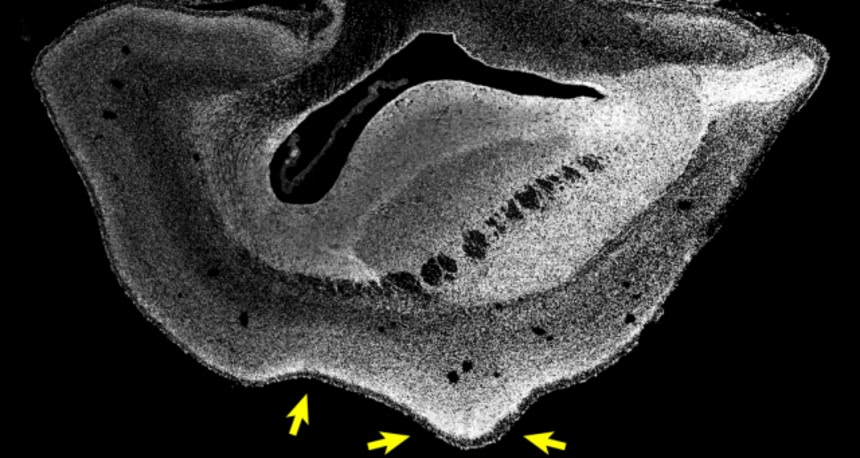

この画像を大きなサイズで見るヒト遺伝子を移植され、通常よりも大きく成長したサルの胎児の脳

image by:Heide et al. / MPI-CBG

この画像を大きなサイズで見る101日後のサルの胎児の脳。矢印はシワの形成が始まっている位置を示す

image credit:Heide et al. / MPI-CBG